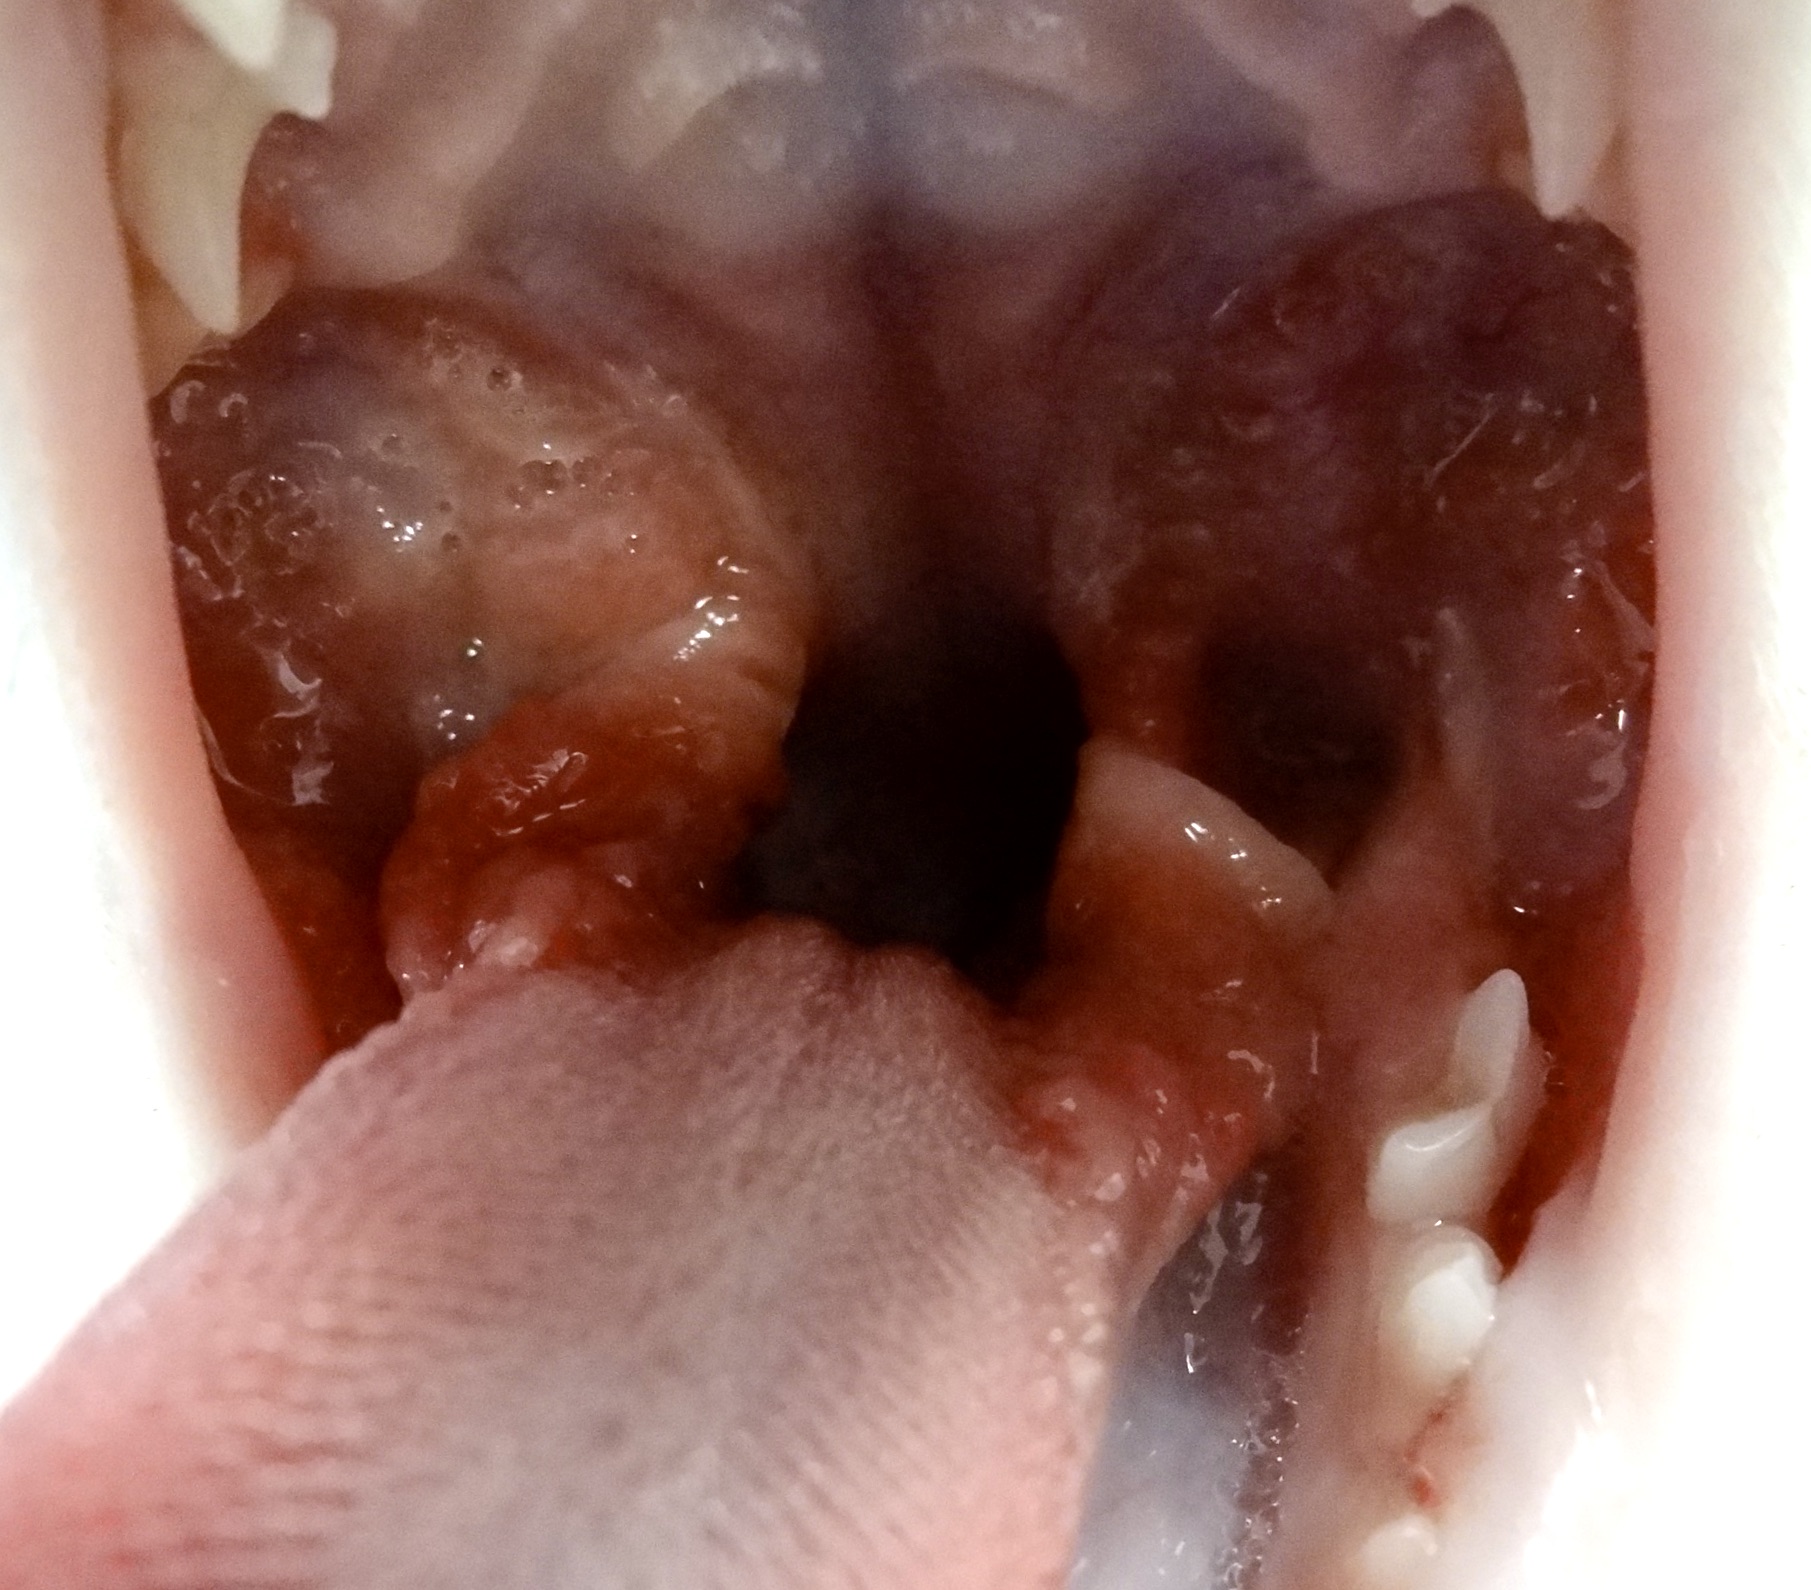

Bon, si on osait, on dirait que jusque-là, ça n’allait pas encore trop mal. (On a bien dit : si on osait). Les inflammations de la gencive et du parodonte sont bien embêtantes, mais restent à peu près localisées autour des dents atteintes ; si on ne traîne pas trop et qu’on met en place des soins dentaires et, si nécessaire, quelques extractions, on récupèrera le plus souvent une bouche saine. Le problème, c’est que le chat ne fait décidément rien comme tout le monde, et que l’inflammation peut, sous certaines conditions que nous détaillons juste après, gagner le fond de la bouche : c’est la stomatite caudale, encore appelée palatoglossite. (Glossite, c’est quand la langue est enflammée, et palato, c’est pour le palais). Et là, ça se traite beaucoup moins bien. Les photos ci-dessous montrent à quoi ça ressemble : on imagine ce que peut endurer le pauvre chat !

Bon alors là, c’est l’horreur complète, Hiroshima après la bombe. Pour ceux qui auraient du mal à s’y reconnaître, tellement c’est modifié, on a le chat en face de nous, bouche ouverte. En haut, c’est le palais, en bas, c’est la langue, de chaque côté on a les dents, et la cavité au milieu, c’est le passage pour les aliments. L’atteinte est symétrique, elle concerne tout le fond de la bouche (= stomatite caudale), en particulier l’arrière du palais, les piliers de la langue (ou piliers du pharynx), et la langue elle-même (= palatoglossite) et peut s’étendre à l’intérieur des joues. La photo de gauche a été prise chez un chat de sept ans, juste avant les extractions dentaires (on en parle plus loin, avec le traitement). À droite, la même en pire, chez une chatte Maine Coon de un an.